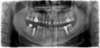

1 implant conique en bas à gauche, à coté d’un fragment de racine inclus dans l’os, remplaçant la 1ère molaire, avec sa vis de cicatrisation

1 implant conique avec sa vis de cicatrisation en bas à droite et cylindrique à gauche, remplaçant les racines de la 1ère molaire droite et gauche, et 1 couronne sur implant en bas à gauche